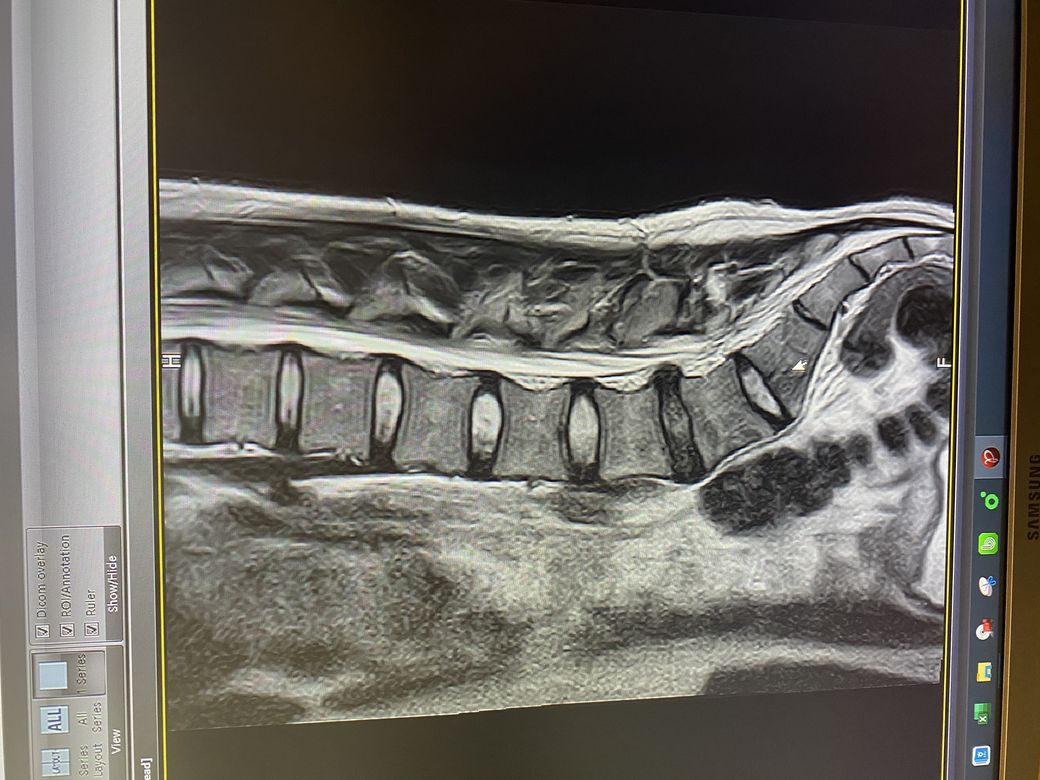

MRI 검사에 대해 1가지 view로 제시된 5컷으로는 의미있는 평가가 어렵습니다.

• 올리신 MRI 사진의 소견으로 보았을 때에는 돌출형으로 디스크가 있으며 신경을 꽤 누르고 있습니다. 축영상을 보아야 더 정확한 판단을 내릴 수 있을 것이지만, 증상이 방사통만 살짝 있을 정도라면 경미한 편이며 헬스를 하는 것에 크게 문제될 것 없습니다. 무리가 가지 않는 선에서 헬스와 같은 코어 근육 강화 운동을 해주어서 허리의 부담을 줄이고 디스크 회복을 시도해보시길 권고드립니다.

L4-L5 사이에 디스크 탈출증이 관찰됩니다.

단면도 함께 봐야 정확한 상태를 파악하는게 가능하지만 이 영상만 봐도 상태가 좋지 않음을 알 수 있습니다.

다른 부위의 디스크는 하얀색으로 보이는데 L4-L5 디스크는 색이 많이 검정색으로 보이는것도 수핵이 빠져나갔음을 알 수 있습니다.